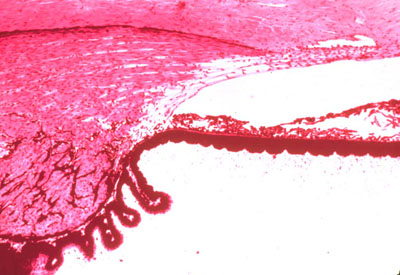

IRIS